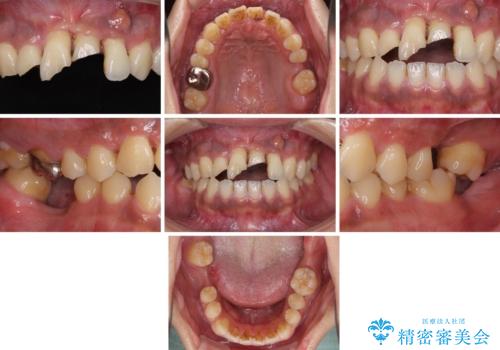

- ソーシャルメディアでのゲームに夢中になっている最中に車と接触し、前歯の抜歯を余儀なくされた患者様です。

初診時では前歯が保存できる可能性も模索しましたが、損傷が激しく3歯を抜去することとなりました。

保存となった隣在歯も神経が失活していており、補綴治療が必要であったので、オールセラミッククラウンにて補綴治療することとしました。

奥歯には元々欠損があり、欠損に伴う咬合不正も認められたため、部分矯正を行った上でインプラント補綴治療も行うこととしました。